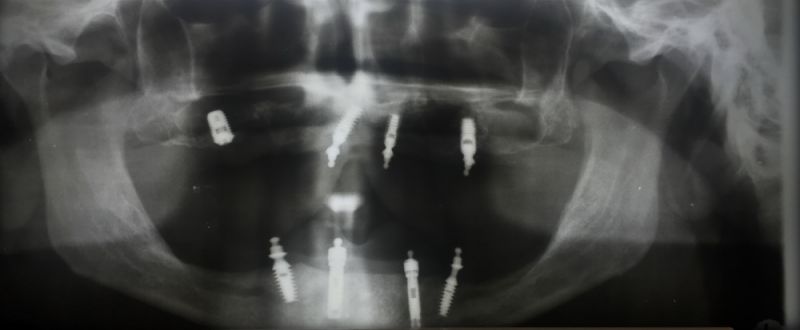

Der Patient erhält heute eine neue implantatgetragene Prothesenrekonstruktion im Ober- und Unterkiefer.

Das Einkleber der O-Ring-Abutments, etwas euphemistisch als "chair-side" beschrieben entwickelte sich zu einem schweißtreibenden Abendvergnügen.